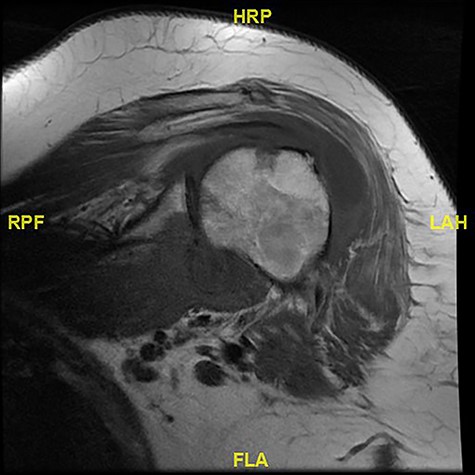

Magnetic resonance imaging (MRI) showed walled off loculations of pus around the proximal humerus with myositis and evidence of septic arthritis.